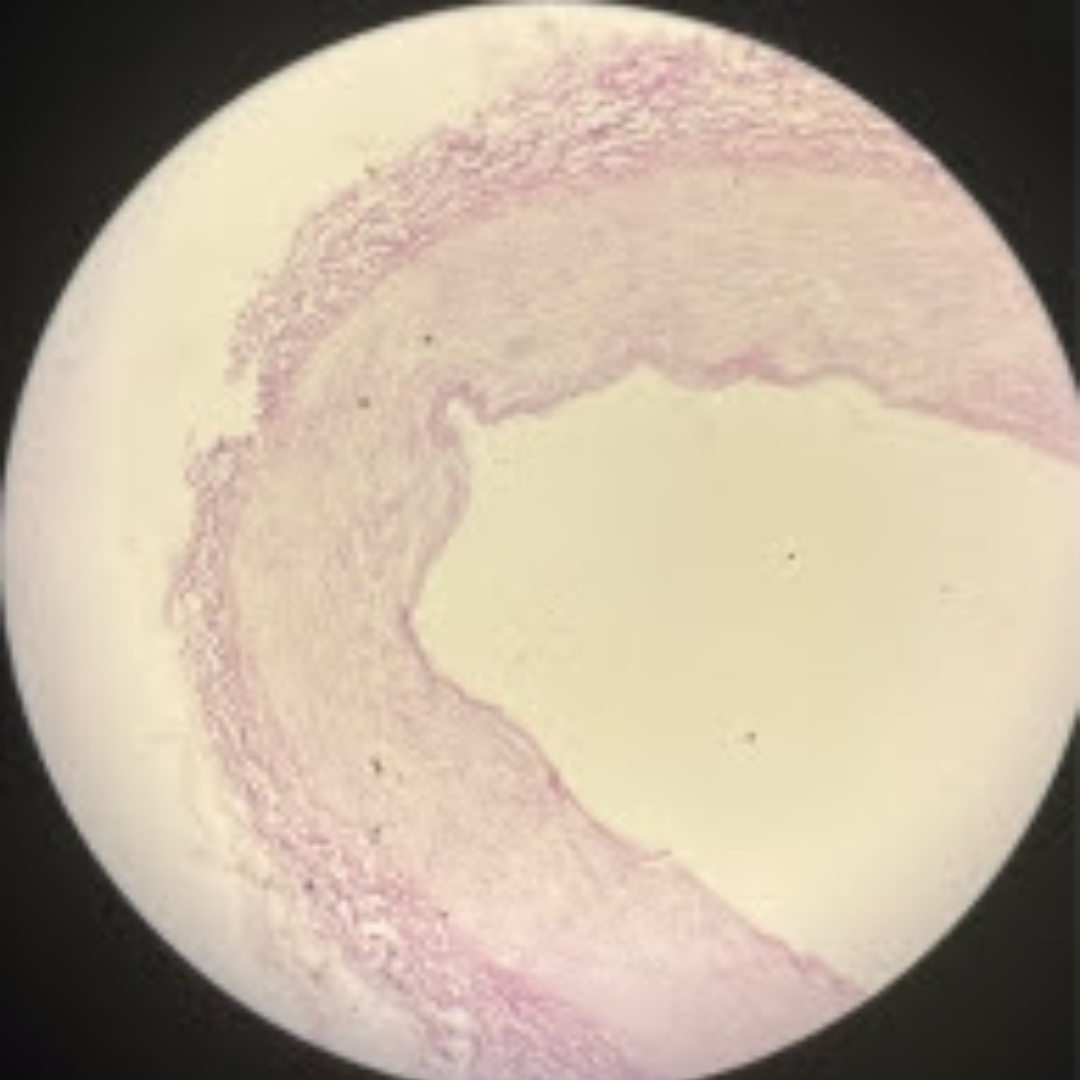

Urinary Bladder (Bladder)

Urinary Bladder (Bladder)

Urinary Bladder (Bladder)

Urinary Bladder (Bladder)